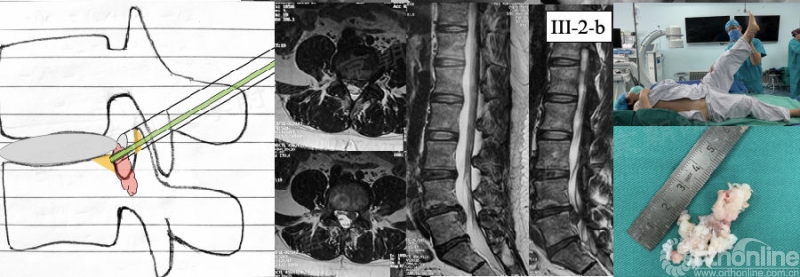

对于向下游离型突出(矢状面III区),此时应进行充分上关节突成型以获得足够的操作空间。不仅如此,在找髓核“尾巴”时可能需要切除部分L5椎体后上缘(黄色区域)。当然也可经椎弓根上缘成型或椎板间入路。